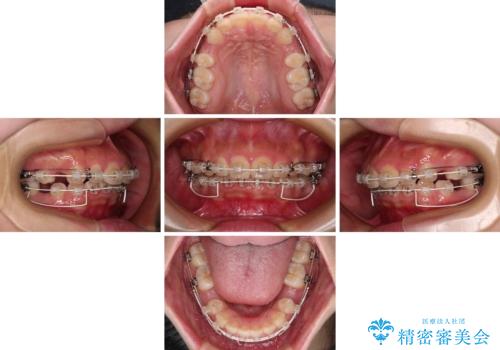

骨格的な上顎前突であり、上下前歯の前後的な距離が大きいため、上顎は左右第一小臼歯を、下顎は左右第二小臼歯をそれぞれ2本抜歯することで前歯が接触するようにし、さらには奥歯の咬み合わせも、より理想的な状態へ近づけていくこととしました。

3年以上はかかる難症例であるため、表側のワイヤー装置にて治療を行うこととしました。